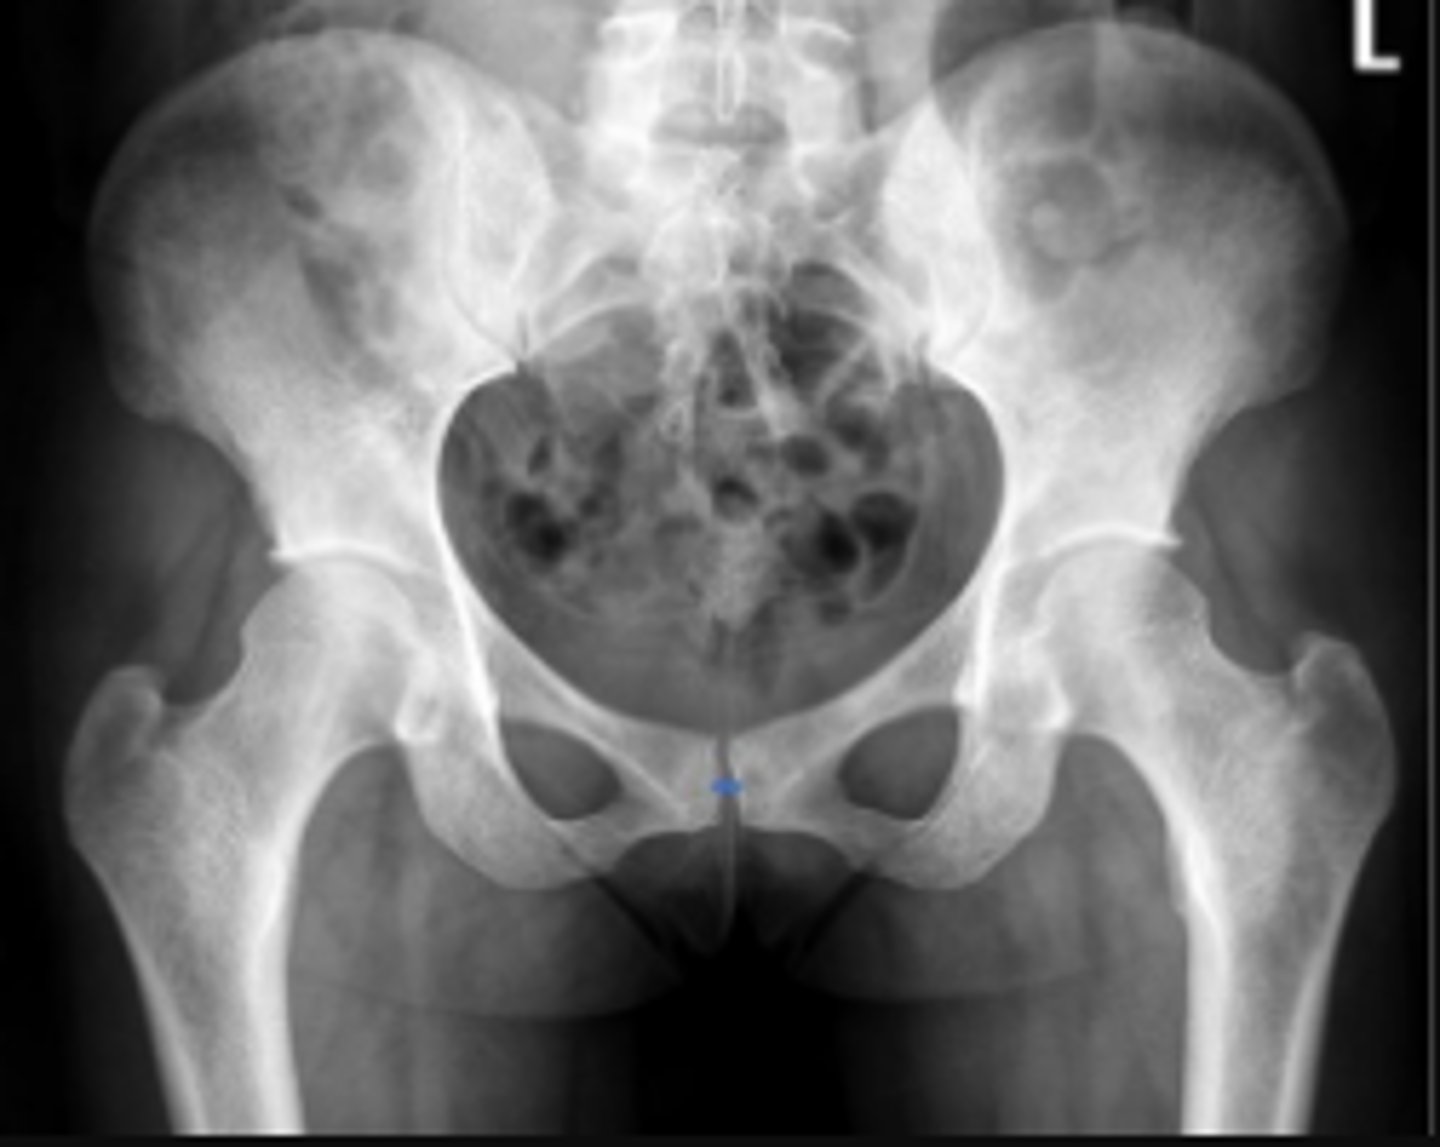

AP pelvis or bilateral hips

What is the name of the radiographic view?

Iliac crest

What are the arrows pointing to?

Sacrum

What is the anatomical structure in between the lines?

ASIS

Left ischial spine

Sigmoid colon

What is outlined?

Right sacroiliac joint

What joint space are the arrows pointing to?

Pubic symphysis

What joint space is the arrow pointing to?

L4/L5 IVD space

Which IVD space is indicated by the arrows?

PSIS

Lesser trochanter of the left femur

Right L5 transverse process

Coccyx

Left obturator foramen

Left superior pubic ramus

Left inferior pubic ramus

AIIS

Soft tissue outline

Right ischial tuberosity

Proximal lateral cortical outline of the diaphysis of the right femur

Right pelvic teardrop

Phleboliths

Greater trochanter of the right femur

Right S3 superior border of the sacral foramen

Greater trochanter of the left femur

L3/L4 IVD space

What IVD space is indicated by the arrows?